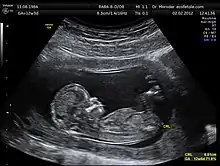

Ultrasonics deals with sound waves in solids, liquids and gases at frequencies too high to be heard by the average person. Specialists areas include medical ultrasonics (including medical ultrasonography), sonochemistry, nondestructive testing, material characterisation and underwater acoustics (sonar).[23]